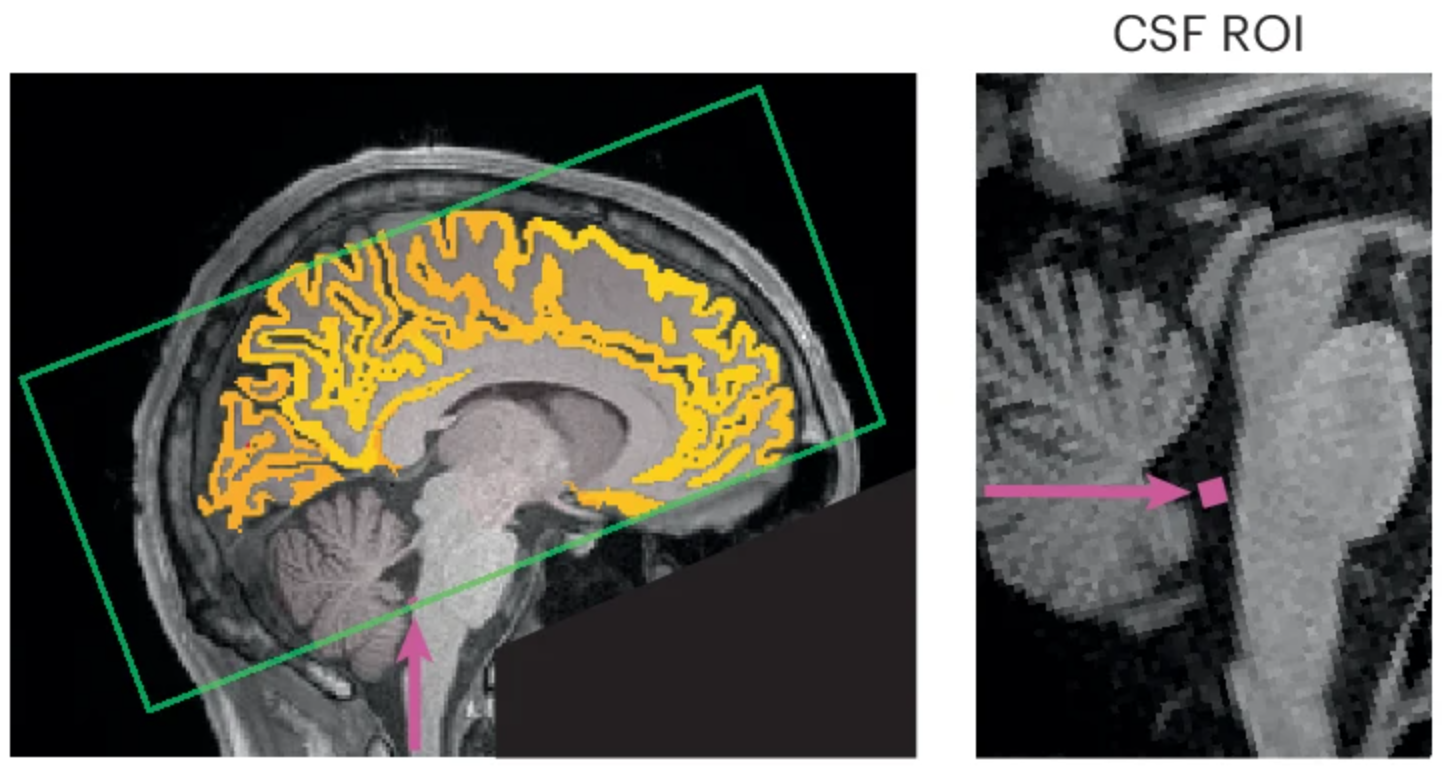

Inside your skull, a clear liquid called cerebrospinal fluid, or CSF, flows around your brain and spinal cord. It is essentially a gentle, rhythmic tide that works to clear out the waste products of each day. Normally, it was thought to happen during a state of sleep, where the brain is entirely free to devote all its energies to maintenance, rather than multitasking. The waves of CSF move in and out, washing away toxins and restoring balance.

But here’s the kicker: if you don’t sleep, those cleaning waves sneak into your awake time. Laura Lewis, associate professor at MIT, was the lead author of a paper published in Nature Neuroscience. Her research team discovered that when your attention is wandering, a wave of CSF washes through your brain, similar to when you’re in deep sleep.

The scans revealed something remarkable. Right when attention faltered, a wave of CSF surged out of the brain. Seconds later, when focus returned, it washed back in. It was like catching the brain mid-rinse.